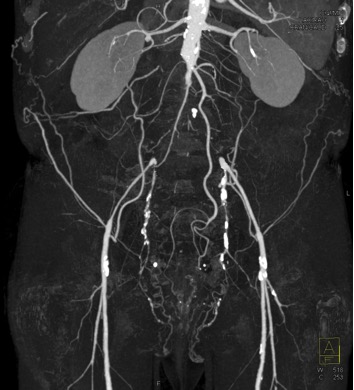

The most likely diagnosis in this case is?

acute occlusion of the aorta

sarcoma arising in the aorta

too early timing of CT Acquisition

Takayasu’s aortitis